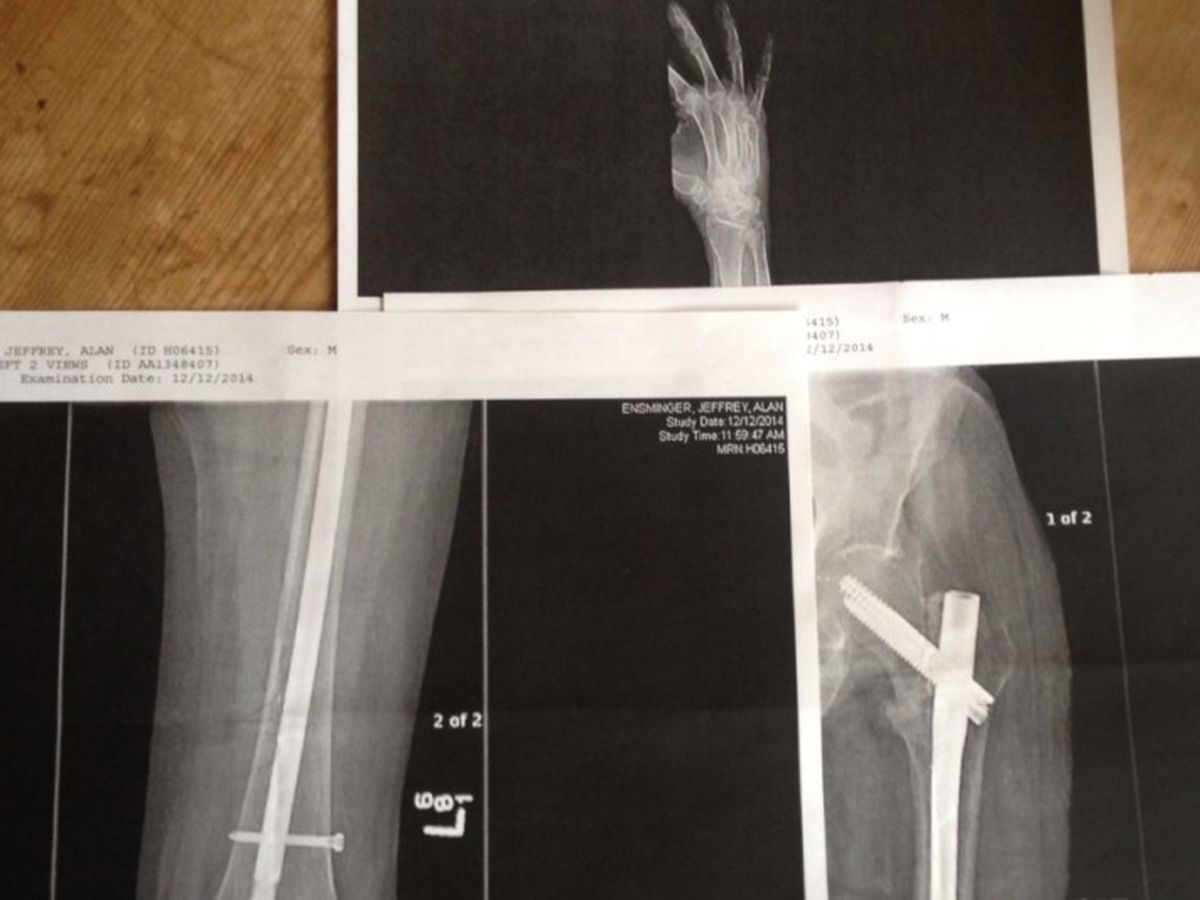

Our father, Jeff Ensminger, has had Grand Mal epilepsy since the age of 16. While its been a lifelong struggle, in the last 3 years his seizures have become more frequent and detrimental, mostly because of osteoporosis, a symptom of his required medication.

In January 2014 our father had 5 unexplained seizures. In June of 2014 he lost most feeling in his legs. While balancing life with medical setbacks we faced a final blow- a seizure that broke his hip. He received surgery, was hospitalized, then sent to a convalescent center for rehabilitation. In October our dad came home. Even with my sister and I checking in daily, he had another seizure in December while healing from the last one, he broke his hand and bruised his hip.